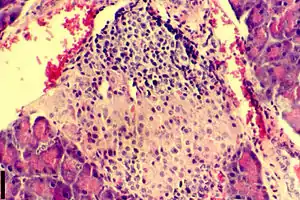

Дефицит инсулина в организме развивается вследствие недостаточной его секреции β-клетками островков Лангерганса поджелудочной железы.

- Гипотетический пусковой момент. Повреждение β-клеток различными диабетогенными факторами и триггирование иммунных процессов. У больных уже определяются антитела к островковым клеткам в небольшом титре, но секреция инсулина ещё не страдает.

- Активный аутоиммунный инсулит. Титр антител высок, уменьшается количество β-клеток, снижается секреция инсулина.

- Клиническая манифестация диабета, в том числе с возможным эпизодом «медового месяца» (периода ремиссии в развитии диабета, который характеризуется повышением количества инсулина вырабатываемого бета-клетками). Секреция инсулина резко снижена, так как погибло более 90 % β-клеток.

- Полная деструкция β-клеток, полное прекращение секреции инсулина.